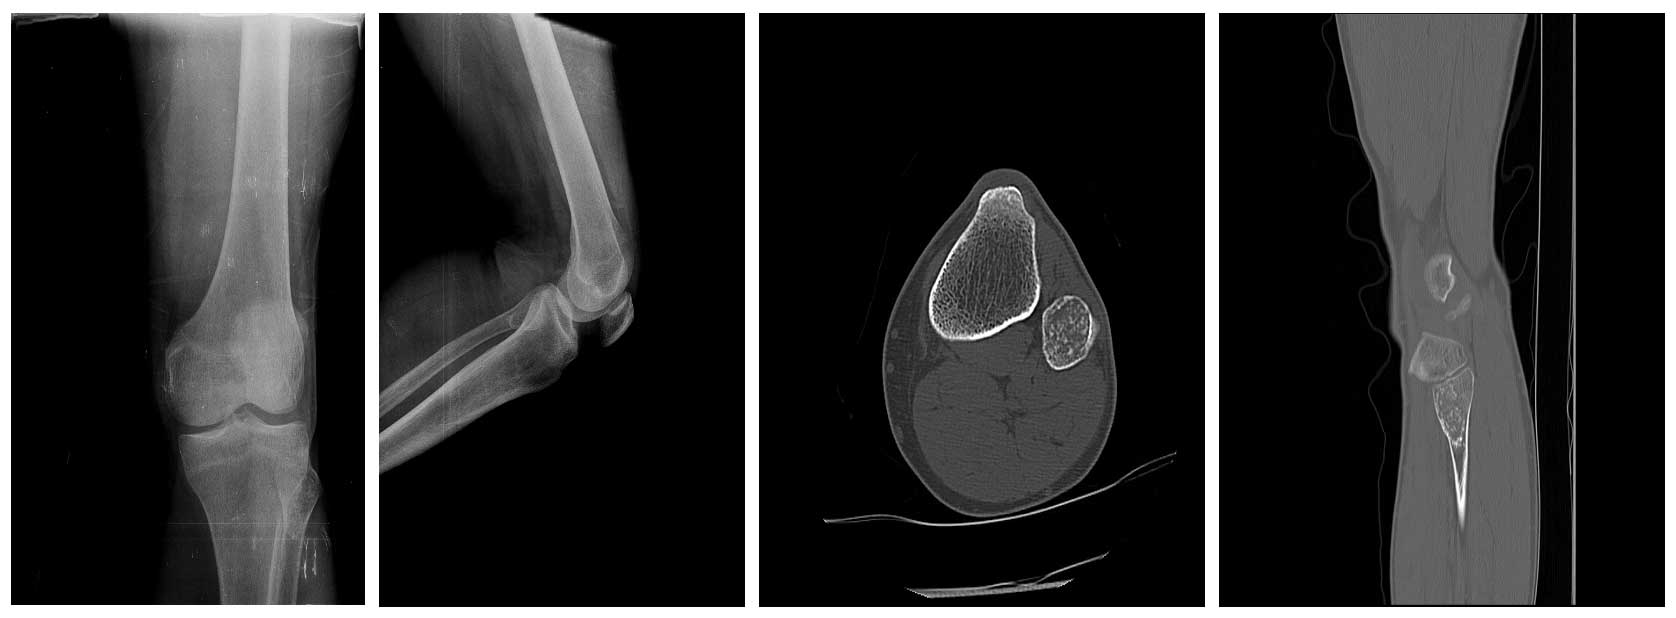

Ameliyat Öncesi: Röntgende ve tomografide kemikte genişlemeye neden olmuş kıkırdak doku tümörü görülmekte.